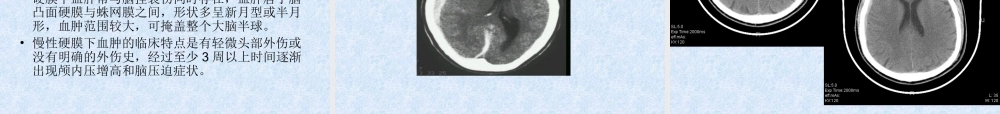

临床急诊的影像学检查与诊断建湖中医院影像科刘玉兵序言•急诊的范畴非常广泛,涉及内、外、妇、儿等临床各科,急诊病情急重,变化迅速。急诊接诊医师对急诊病人的诊治途径常常是从症状的诊断与鉴别诊断开始的,通过症状的初步诊断拟定相关的实验室、生化及影像学检查方法,然后针对这些检查结果及临床症状进行综合分析,得出结论,进行救治。目前我院现有的影像科设备•直接数字化摄影系统(DR)•GE双排螺旋CT•数字X光胃肠机•OPERMARK4000(MRI)DR数字胃肠机双排螺旋CTMRI•X线检查一直是急诊影像检查的主要内容,随着影像技术的发展,CT及MRI的急诊应用也越来越多,如何在急诊医学中应用好这些影像技术,怎样规范检查,是目前我们影像科和急诊临床共同面临的课题。•首先我们临床医生一定要掌握好各项医技检查的适应症和如何规范地开出检查单,以便又快又好地帮助患者得到准确诊断,得到及时的治疗。•其次急诊工作是高风险的工作,医学影像科作为重要的医技科室,对各科急诊的诊断处理起着至关重要的作用。•医学影像科的急诊工作是临床急诊中较为重要的组成部分。医学影像科急诊处理的及时性与准确性将直接影响到临床急诊的处理。•急诊工作要求医学影像科医技人员必须具备扎实的检查技术和检查技巧,简化工作流程,尽可能缩短患者在医学影像科的就诊时间,争分夺秒地为患者的抢救及治疗赢得宝贵时间。影像学检查在急诊中的应用•在颅脑急症中的应用•在胸部急症中的应用•在腹部急症中的应用•在脊柱急症中的应用•在四肢关节急症中的应用颅脑急症中的应用•常见的•创伤性颅脑急症•血管性颅脑急症•感染性颅脑急症创伤性颅脑急诊的应用•首选CT检查•CT在创伤性颅脑急诊诊断中属常规和首选检查方法,可清楚显示脑挫裂伤、急性脑内血肿、硬膜下及硬膜外血肿、颅面骨骨折、颅内金属异物等,而且比其它任何方法都要敏感。•CT检查获得的诊断信息比X线平片更多,它可同时显示颅骨骨折及颅内损伤情况,这对制定治疗方案,争取抢救时间显得更重要。脑挫裂伤•脑挫裂伤是指颅脑外伤所致的脑组织器质性损伤,是最常见的颅脑外伤之一。•多发生于着力点及其附近,也可发生于对冲部位,常并发蛛网膜下腔出血。•病理改变包括脑外伤引起的局部脑水肿、坏死、液化和多发散在小出血等变化。•临床表现有伤后头痛、恶心、呕吐和意识障碍。硬膜外血肿•颅脑出血积聚于颅骨与硬膜之间,称为硬膜外血肿。•约占各种颅脑外伤血肿的1/3,多为急性或亚急性,...